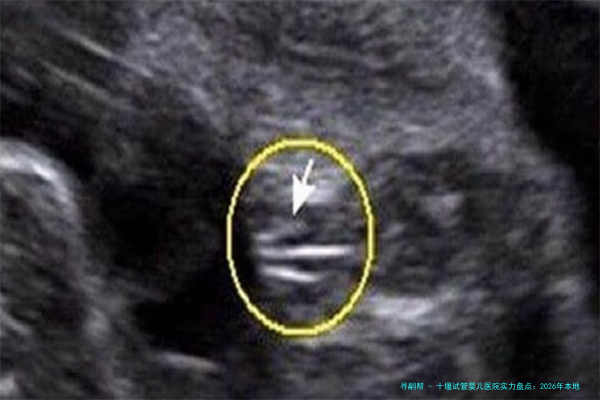

验孕及早期B超检查500200350250-450